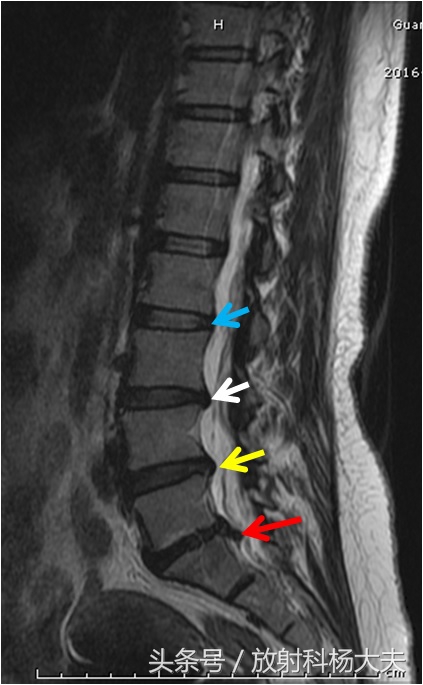

放射科大夫经常在一个病人身上,看到三种不同的表现,比如下图为一老人的腰椎MRI,从上往下,不同的标示,分别代表正常椎间盘,椎间盘膨出,椎间盘突出和椎间盘脱出。关注,影像报告上只诊断具体类型,而不诊断“椎间盘突出症”,少了一个“症”字,其中的内涵,就代表放射科和骨科的差距。